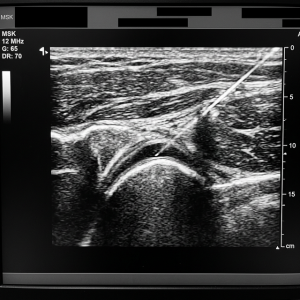

1. Real-Time Tracking

We use high-resolution ultrasound probes to “see” the needle tip as it moves through the tissue. We watch it enter the joint capsule or the tendon sheath, ensuring the medication is deposited exactly where the pathology is located.